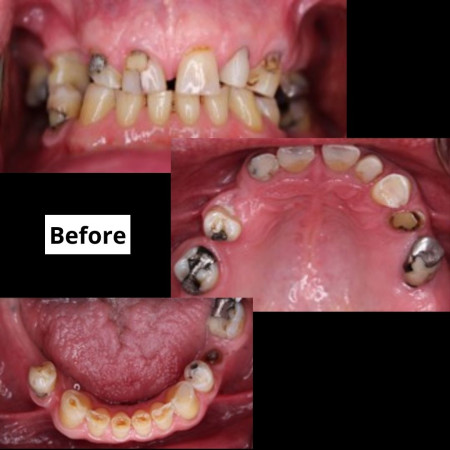

Aesthetic enhancement of the smile

Smile designing is an area of dentistry we are very proud to offer to our patients. This will be done after a careful assessment of the teeth and soft tissues and these patients will be seen by a panel of Danthaja experts to give you the best aesthetic outcomes. Newest software aided by CAD-CAM technology will be employed in these cases to optimize and pre-visualize the outcome.

Full-mouth rehabilitation of tooth wear

Tooth wear is becoming a common problem in the contemporary population. This is commonly seen among young patients because of the excessive use of fizzy drinks and reflux medical conditions like gastritis. In Sri Lanka, this is commonly evident in the elderly population due to untimely extractions of posterior teeth. Management of tooth wear needs proper understanding of the causes, meticulous planning and proper execution of the plan. Otherwise, any treatment will be futile. Danthaja will offer you the best treatment options that would guarantee the best aesthetic outcomes with functional stability in tooth-wear cases.